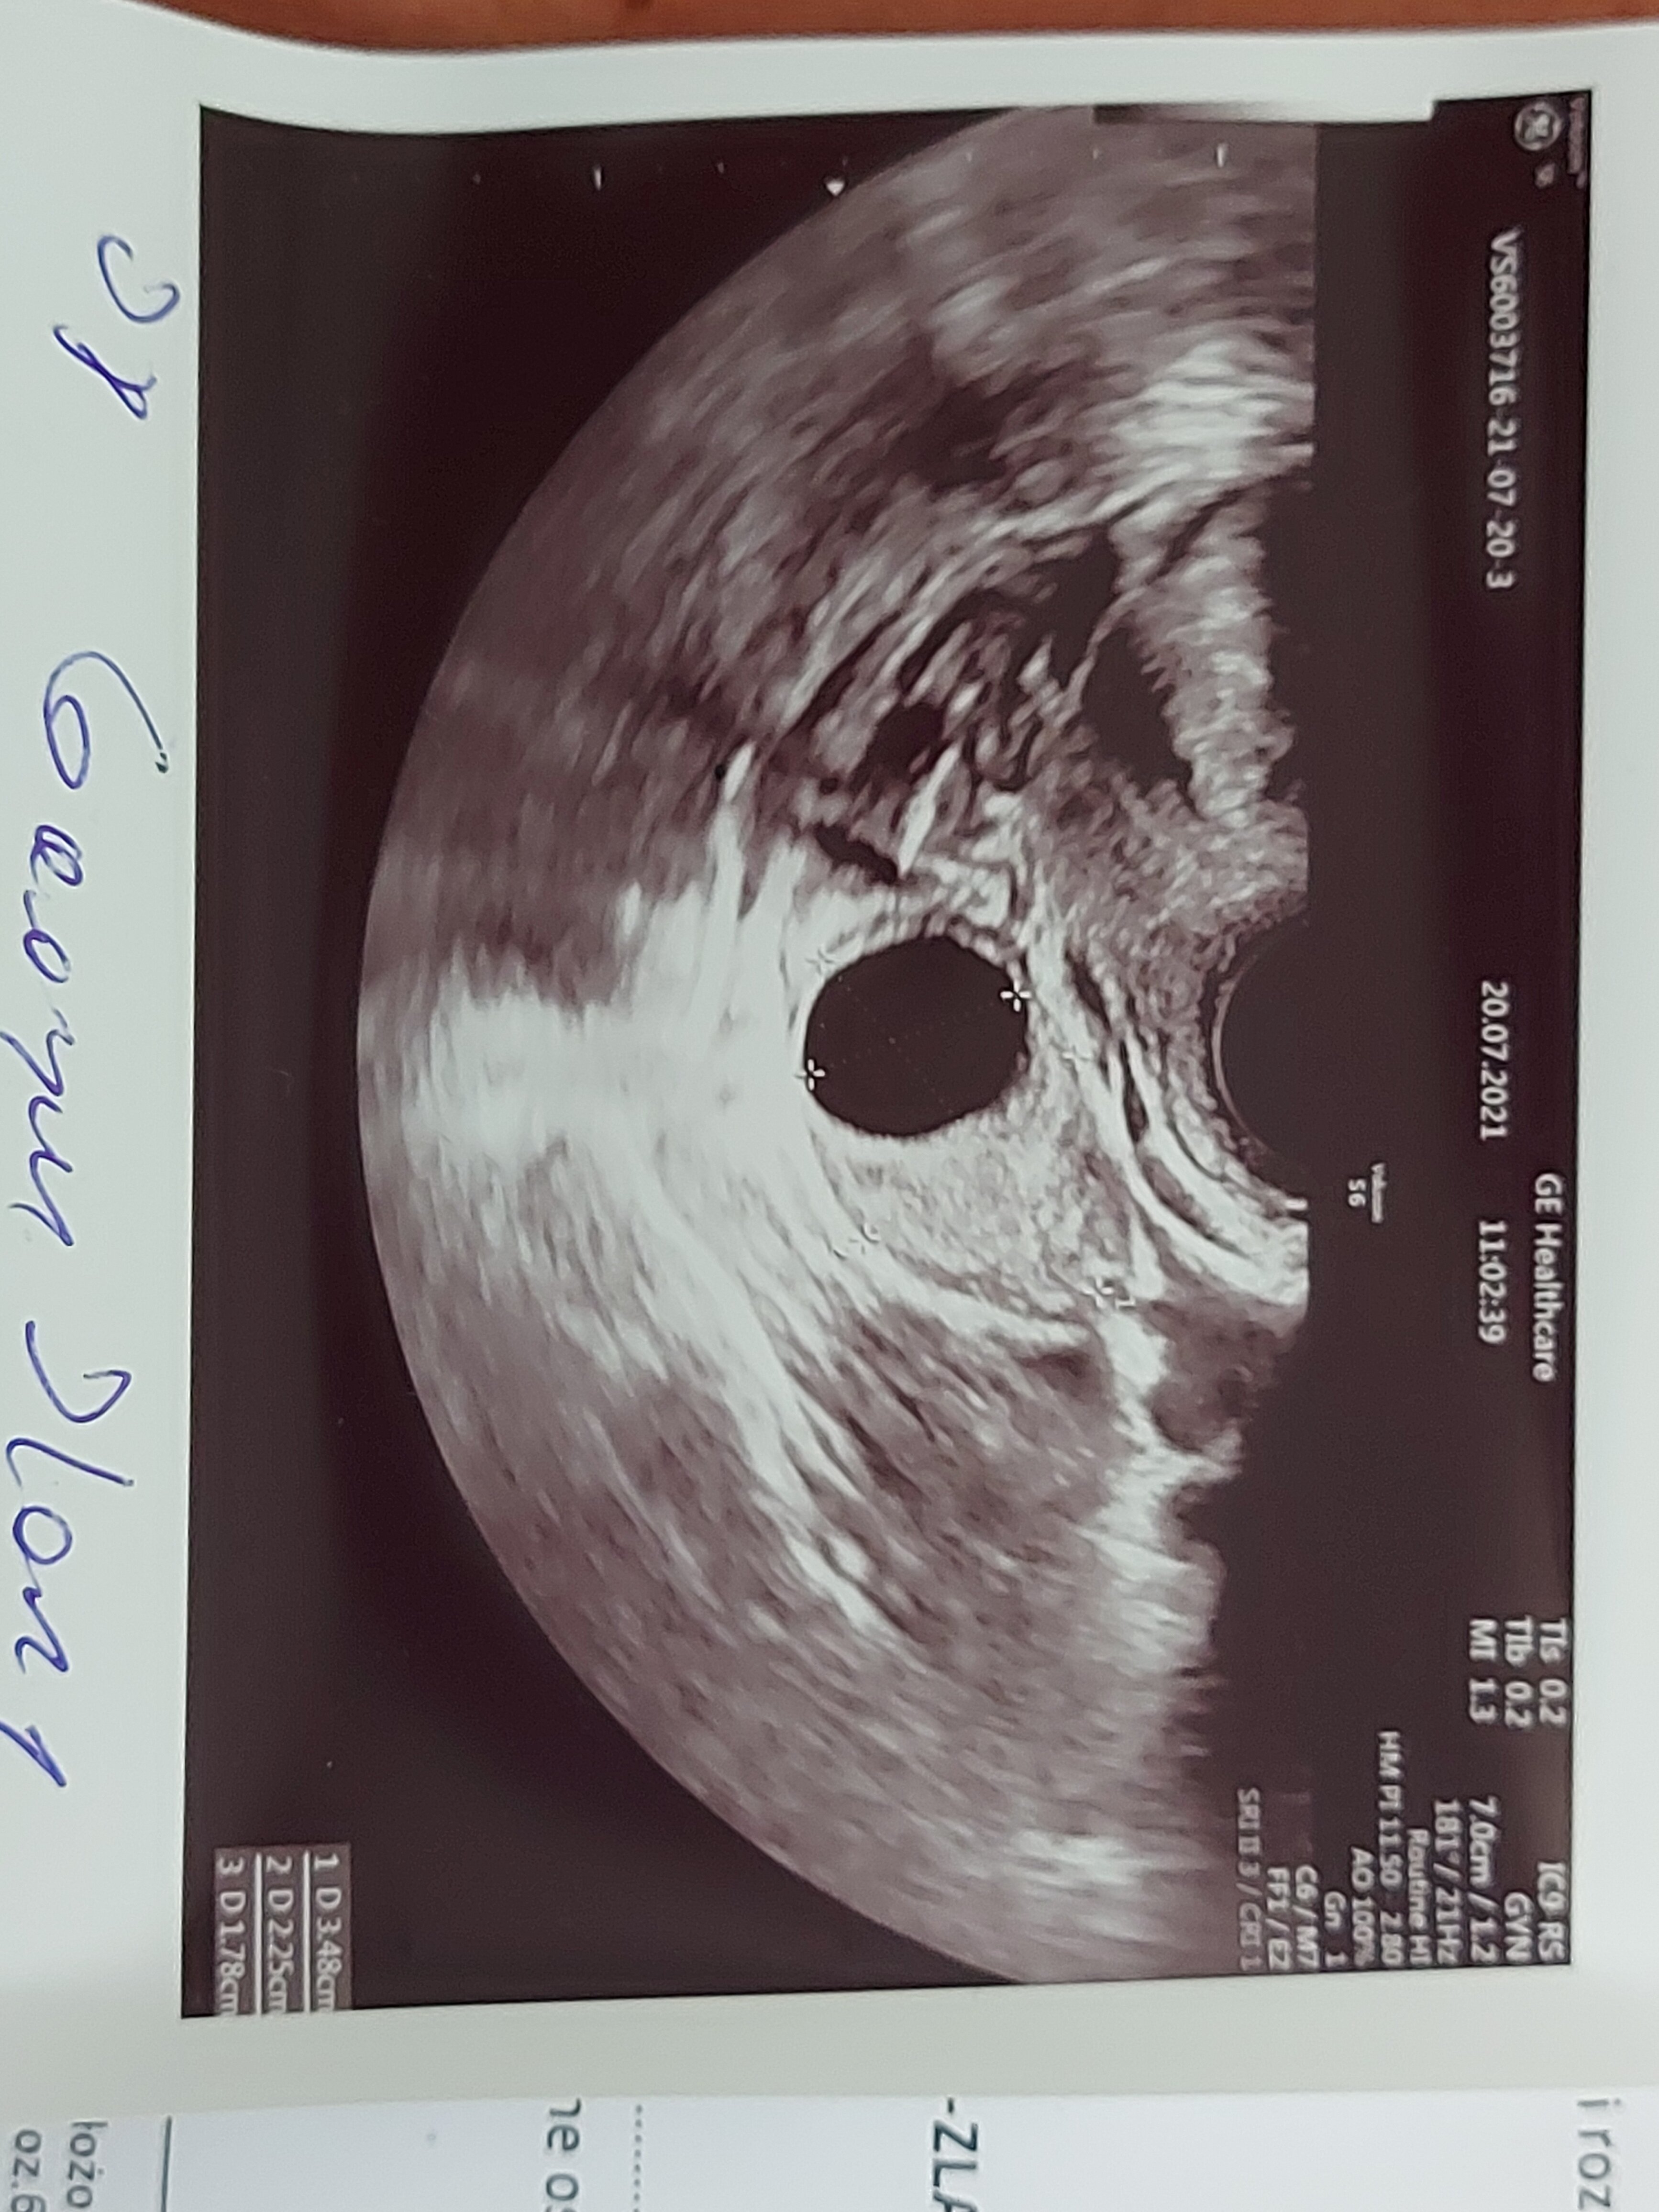

Czesc jestem w 6tc i po ostatniej wizycie pani doktor która najpierw mnie skomentowała ze w krótkich spodenkach się nie przychodzi do lekarza bo ona czuje się obrazona pierwszy raz się z czym takim spotkalam zdenerwowana przebadała mnie i mówi ze tu coś jest nie tak bo nie ma serca ani głowy ze chyba bezczaszkowiec I ona się pod tym nie podpisze i dala mi skierowanie do szpitala na szczegółowe badanie USG ( na skierowaniu napisala niewyraźny obraz usg chyba ciąża obumarla)Poszlam ale p.doktor powiedzial ze dopiero za tydzień możemy zobaczyć czy wszystko ok bo to wczesna ciąża.Chce jeszcze dodać ze tydzień temu bylam prywatnie i lekarz na usg powiedział ze widzi sam pęcherzyk.Co Wy o tym myślicie i uważacie bo jestem bardzo zdenerwowana szczegółowe badanie bede miec 4sierpnia.Jestem załamana.Ilona 40lat druga ciąża.

• 20210721_092425.jpg

20210721_092425.jpg

1,5 MB · Wyświetleń: 573